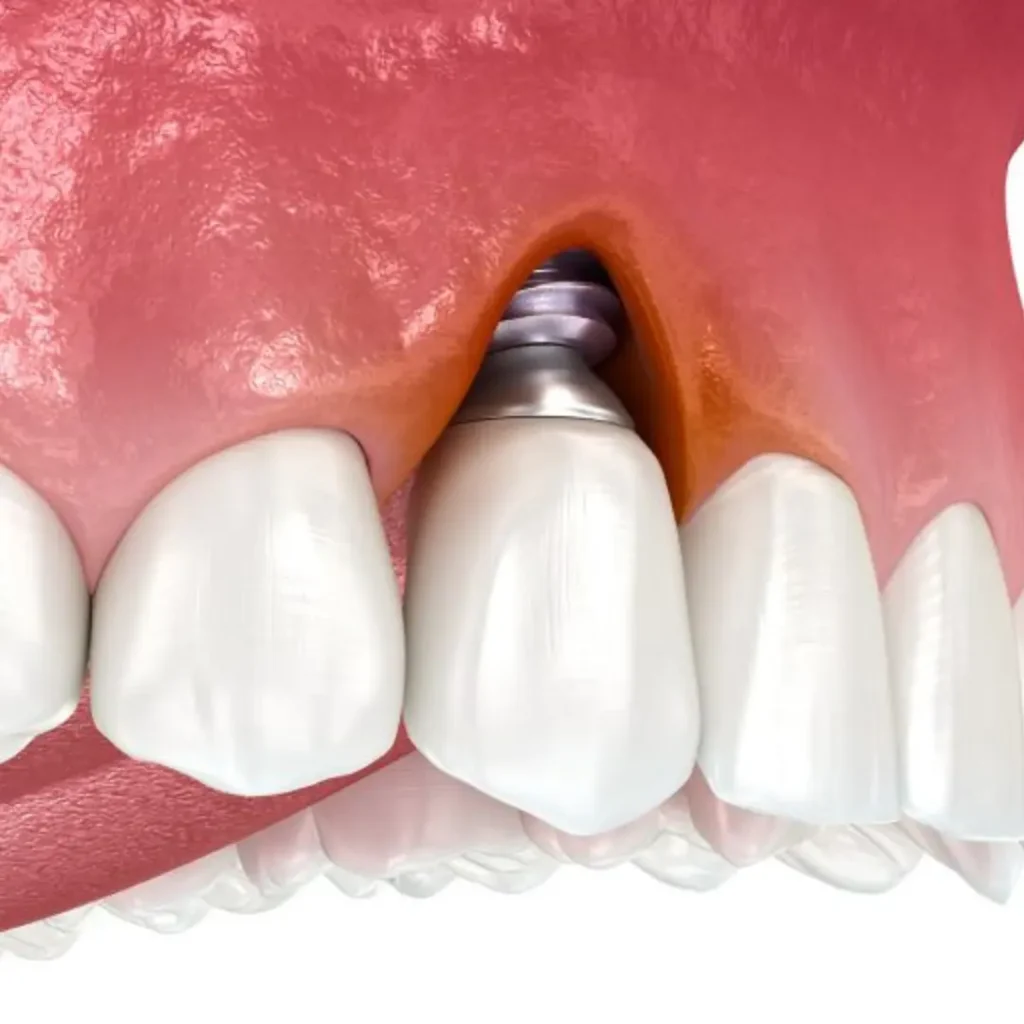

Cracked or fractured implants

Loose or shifting dental implants

The implant crown fell off or broke

Infection or pain around an implant

A dental implant emergency includes a loose dental implant, pain or swelling around the implant, a broken crown, or sudden implant failure due to trauma or infection. If left untreated, these issues may affect surrounding soft tissue, bone, or even your overall health, so prompt emergency dental care is crucial.

Yes. Gum disease (also called peri-implantitis when around an implant) can compromise the success of your dental implant by damaging the surrounding soft tissue and bone. Early detection and treatment are key to saving the implant.